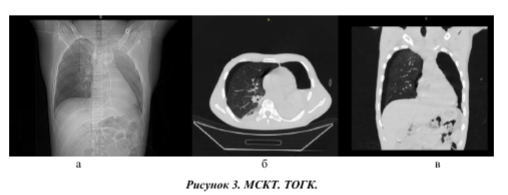

На топограмме (а) хорошо визуализируется тотальный пневматоракс слева. На аксиальном срезе (б) кроме пневмоторакса определяется и гемоторакс (горизонтальный уровень жидкости).

На фронтальном срезе можно увидеть, что воздух имеется и в плевральной полости правого легкого.